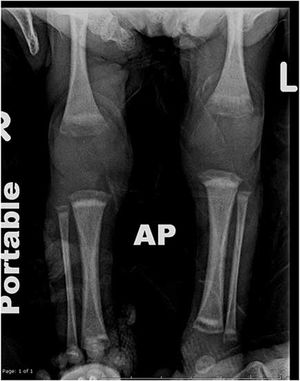

Clinical History: A 29-year-old G1P0 female with poor prenatal care who birthed a 29-week infant via vaginal delivery. The infant had a weak cry, minimal respiratory effort, and an Apgar of 6 at one minute and 8 at five minutes. The baby was intubated and sent to the NICU.